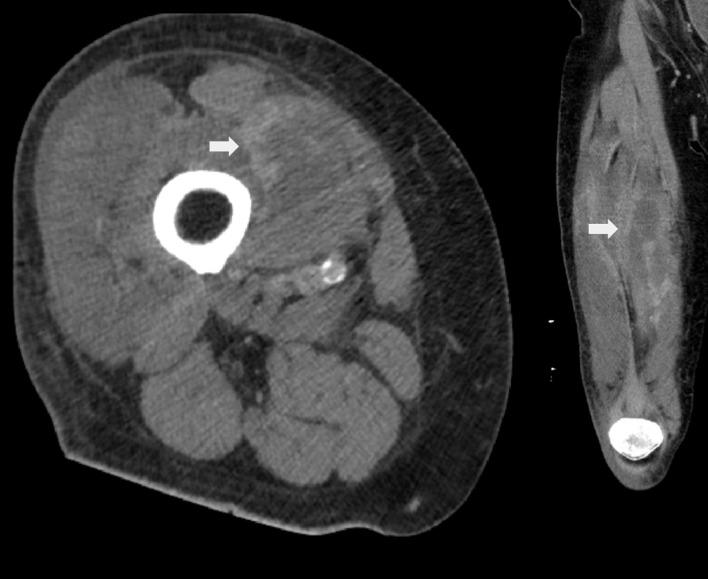

Skeletal muscle metastases are uncommon, and metastases of urothelial carcinoma to the skeletal muscle are particularly rare. The most common presentation of skeletal muscle metastases is a focal mass, but their clinical and radiographic findings can be diverse. We present an unusual case of a 71-year-old male without prior known history of malignancy who presented with skeletal muscle pain with imaging most consistent with an inflammatory or infectious process but was ultimately determined to be metastatic urothelial carcinoma from the bladder. This case demonstrates the need to keep an expanded differential for muscular pain, particularly when initial treatments are ineffective.

骨骼肌转移瘤并不常见,而尿路上皮癌转移至骨骼肌则尤为罕见。骨骼肌转移瘤最常见的表现是局灶性肿块,但其临床和影像学表现可能多种多样。我们报告一例罕见病例,一名71岁男性,既往无恶性肿瘤病史,因骨骼肌疼痛就诊,影像学检查结果最符合炎症或感染性病变,但最终确诊为膀胱尿路上皮癌转移。该病例表明,对于肌肉疼痛需要考虑更广泛的鉴别诊断,尤其是在初始治疗无效时。